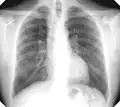

There are three key elements to the diagnosis of silicosis. First, the patient history should reveal exposure to sufficient silica dust to cause this illness. Second, chest imaging (usually chest x-ray) that reveals findings consistent with silicosis. Third, there are no underlying illnesses that are more likely to be causing the abnormalities. Physical examination is usually unremarkable unless there is complicated disease. Also, the examination findings are not specific for silicosis. Pulmonary function testing may reveal airflow limitation, restrictive defects, reduced diffusion capacity, mixed defects, or may be normal (especially without complicated disease). Most cases of silicosis do not require tissue biopsy for diagnosis, but this may be necessary in some cases, primarily to exclude other conditions.

For uncomplicated silicosis, chest x-ray will confirm the presence of small (< 10 mm) nodules in the lungs, especially in the upper lung zones. Using the ILO classification system, these are of profusion 1/0 or greater and shape/size "p", "q", or "r". Lung zone involvement and profusion increases with disease progression. In advanced cases of silicosis, large opacity (> 1 cm) occurs from coalescence of small opacities, particularly in the upper lung zones. With retraction of the lung tissue, there is compensatory emphysema. Enlargement of the hilum is common with chronic and accelerated silicosis. In about 5–10% of cases, the nodes will calcify circumferentially, producing so-called "eggshell" calcification. This finding is not pathognomonic (diagnostic) of silicosis. In some cases, the pulmonary nodules may also become calcified.

Chest X-ray showing uncomplicated silicosis